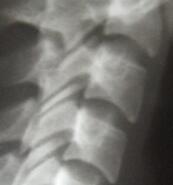

早晨起床是腰脊发僵,活动不利,称之晨僵。强直性脊柱炎常见症状有哪些?少数人有低热、疲劳和体重下降,个别病人可出现贫血、少数急性发病者也可有高热,四肢受累较重者,很快即可卧床不起...[详细] 2024-10-08

胸椎受累时,表现为背痛、前胸和侧胸痛,最后可呈驼背畸形。如肋椎关节、胸骨柄体关节、胸锁关节及肋软骨间关节受累,则呈束带状胸痛,胸廓扩张受限,吸气、打喷嚏或咳嗽时胸痛加重。严重者胸廓保持在呼气状态,胸廓扩张度较正常人降低50%以上,因此只能靠腹...[详细] 2024-10-08